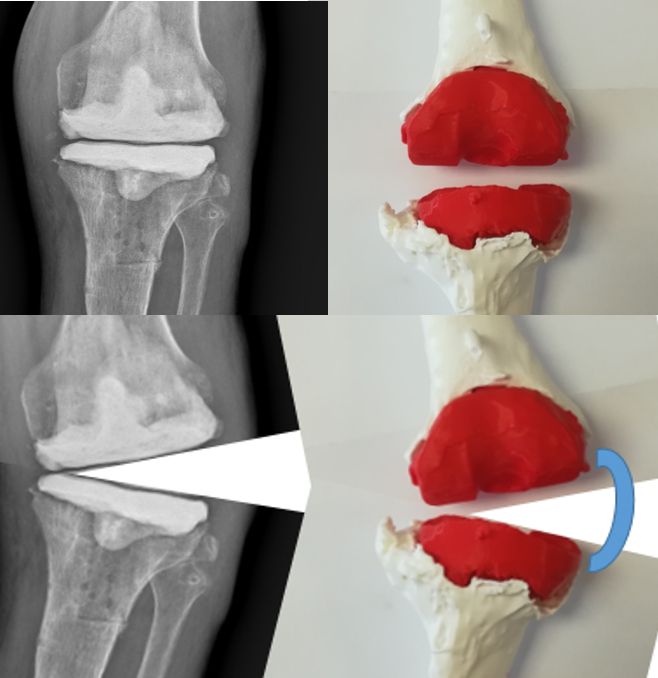

The development of three-dimensional (3D) printing technology is proposed for better planning of complex revision surgery. Regarding preoperative revision planning, conventional radiographs often underestimate the degree of bone loss, while computed tomography (CT) can provide additional details, but the surgeon is limited in his or her ability to clinically translate this information into surgical execution (Fig. 1).

Once the model is assembled, the surgeon can go to the operating room with peace of mind, knowing that only minimal modifications will be required. Nevertheless, this type of preoperative planning allows for a significant reduction in the instruments and materials used during surgery. The lack of capsular and ligament components is a limitation of this technique and therefore a way to implement this in the model needs to be investigated, for example by using varus-valgus stress radiographs to reproduce the same amount of laxity in the model (Fig. 21).